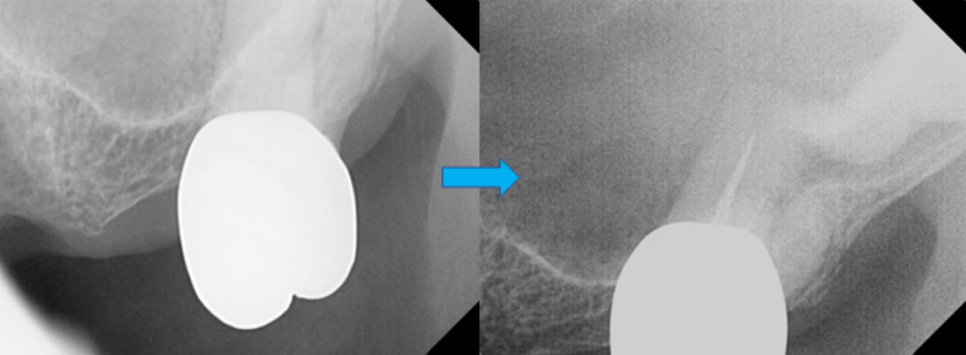

위에 앞니 임플란트를 심은 지 1달이 지났습니다.

한달까지가 임플란트와 치조골 뼈의 골유착에 가장 중요한 시기입니다.

앞니만 자세히 볼 수 있는 치근단 엑스레이를 찍어서

임플란트의 상태를 확인합니다.

임플란트와 뼈의 유착관계가 좋습니다. 뼈도 잘 차고 있습니다. ^^

두달만 더 기다리기로 합니다.

확대해서 보는 치근단 엑스레이 보시면,

하얗게 뿌리부분에 신경치료 재료가 잘 들어가

잘 마무리 된 것을 볼 수 있습니다.